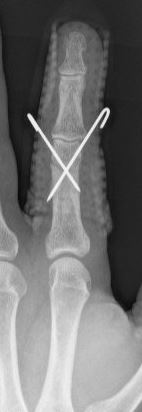

Voor een operatie van de hand of vingers zijn er meerdere opties. Er kan gebruik worden gemaakt van zeer kleine plaatjes en schroeven voor het vastzetten van de breuk. Soms wordt er ook gebruik gemaakt van dunne metalen pennen of van een fixatie aan de buitenkant (zogenaamde ‘externe fixateur’). Welke operatie u uiteindelijk krijgt, is afhankelijk van de eigenschappen van de breuk, de toestand van de huid en de spieren en de voorkeur van uw traumachirurg.